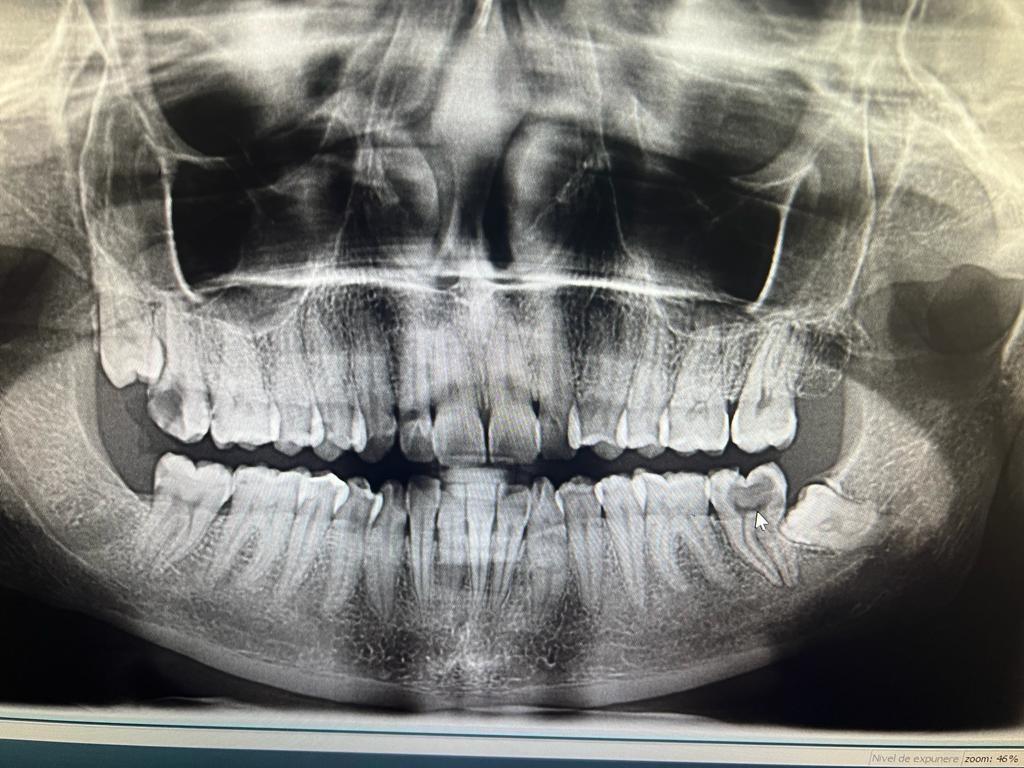

Clinica LUY ESTHETIC ART defineste parodontoza ca fiind rezultatul direct al placii dentare, care se depune pe suprafata dintilor, dar si in apropiere de marginea gingivala. Aceasta boala duce la pierderea dintilor, chiar daca ei sunt aparent sanatosi si nu prezinta carii. Edentatiile, afecteaza vorbirea, aspectul, dar si capacitatea de a mesteca.

Boala parodontala are un caracter progresiv. Pentru cazurile mai grave, recomandam tratamentul parodontal chirurgical rezectiv sau regenerativ.

O igiena bucala necorespunzatoare, fumatul, placa bacteriana si alte boli generale, permit bacteriilor sa se dezvolte in cavitatea bucala.